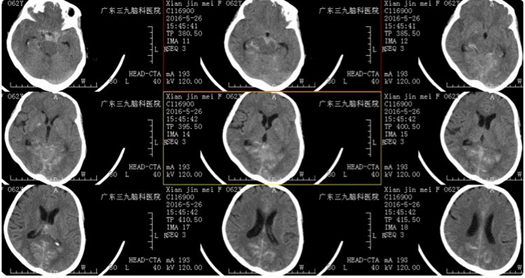

Female,62Y,ASAH

CT示:鞍上池、纵裂池、双侧小脑幕及幕上池内高密度影

CTA提示:1、右侧小脑后下动脉起始部动脉瘤 2、右侧后交通动脉瘤